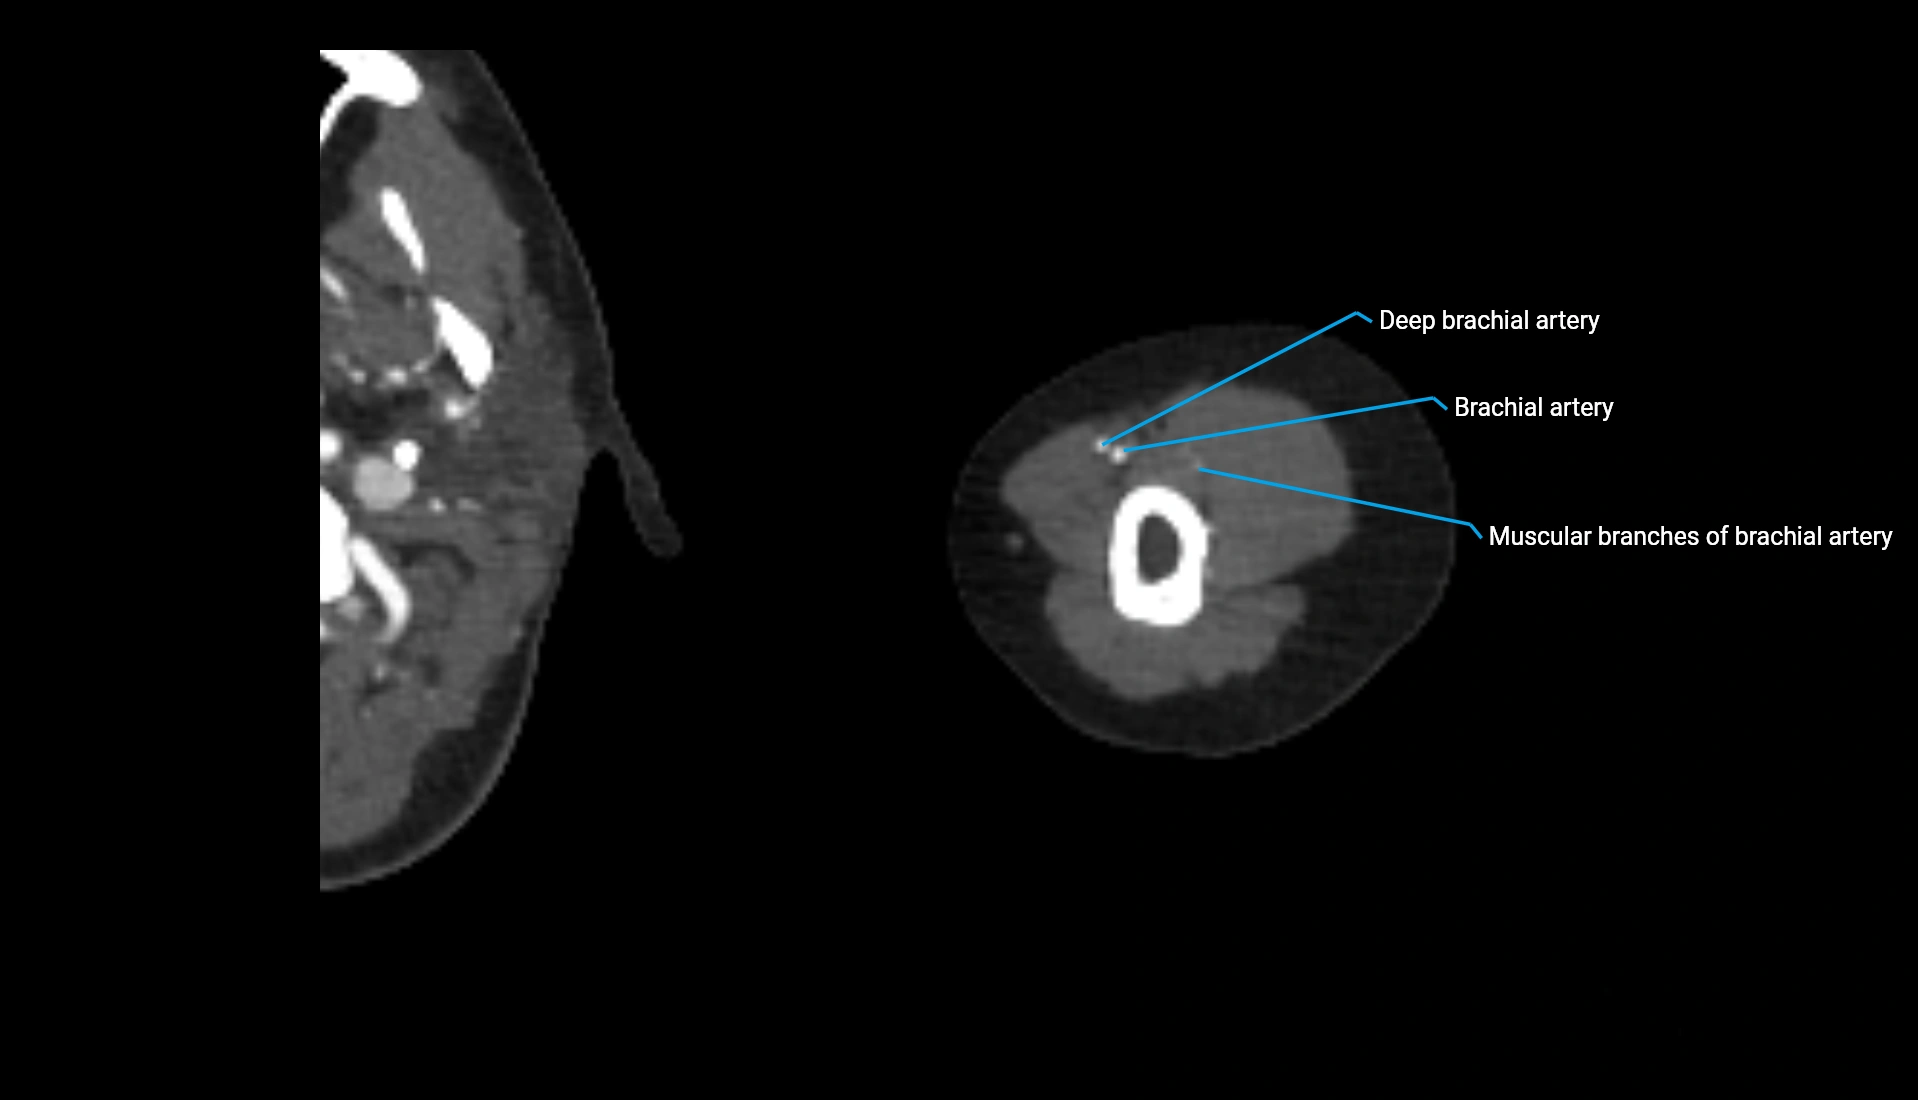

CT Appearance

Non-Contrast CT:

• Cortex: High-density, sharply defined

• Subchondral bone: Dense cancellous matrix

• Articular surface: Smooth concave contour articulating with the capitellum

• Excellent for evaluating bone integrity, alignment, and subtle fractures